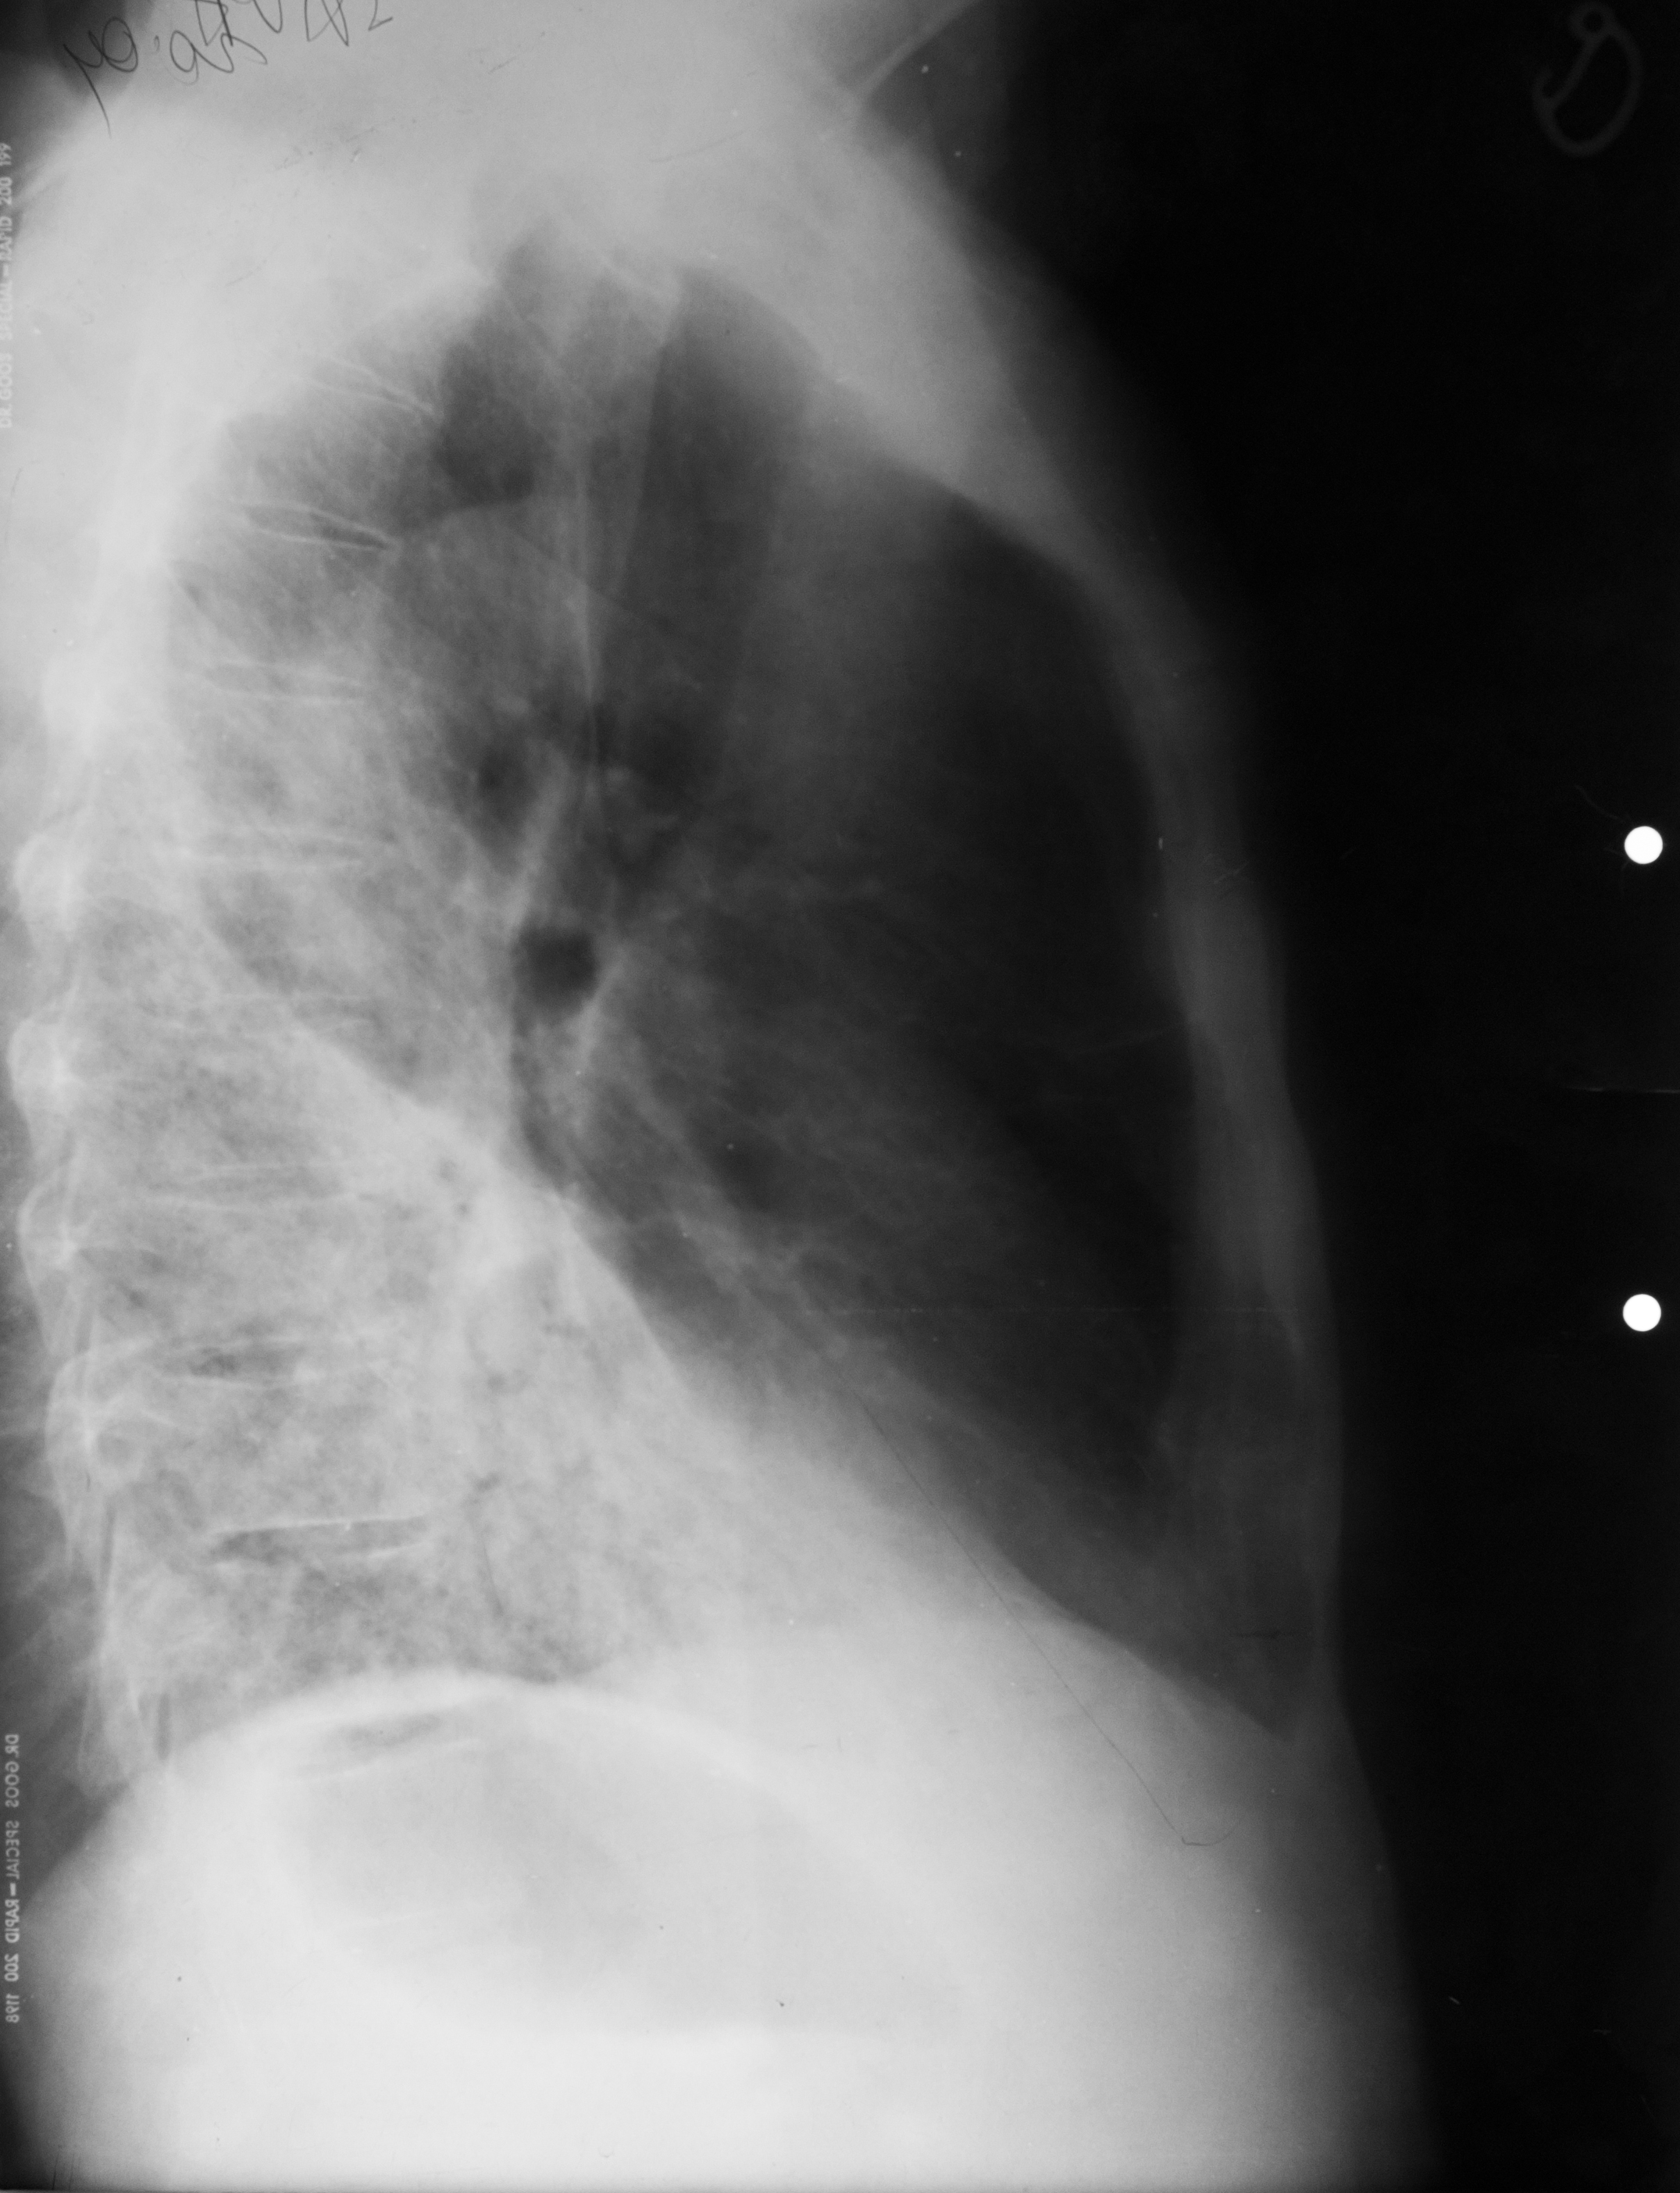

Rx toraco-mediastino-pleuro-pulmonar,de profil – opacitate

CHIST SUPRAINFECTAT VĂZUT DIN PROFIL (radiografie de profil)

Imagine hidroaerică,mixtă

ABCES PARȚIAL DETERJAT PE RADIOGRAFIA DE PROFIL